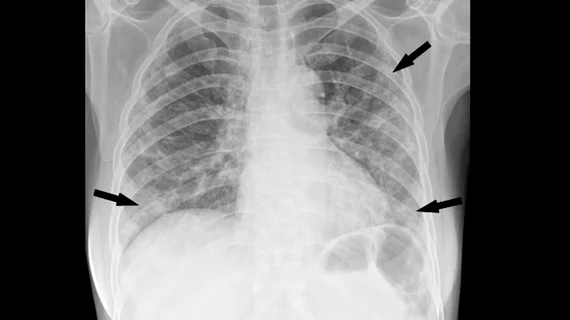

Вскоре после начала пандемии COVID-19 медицинские работники быстро осознали, что визуализация является жизненно важным инструментом как для диагностики вируса, так и для определения тяжести заболевания. Компьютерная томография грудной клетки стала критически важной для оказания медицинской помощи пациентам, но более доступные исследования, такие как рентгенография грудной клетки, были необходимы, особенно в условиях ограниченных ресурсов.

Недавно исследователи изучили, могут ли предварительно обученные приложения, разработанные для оценки рентгенограмм грудной клетки на предмет заболеваний, отличных от COVID-19, выявлять признаки вируса. Они проверили свою теорию, используя коммерческое программное обеспечение на основе искусственного интеллекта, первоначально разработанное для обнаружения легочных узлов на рентгенограммах грудной клетки. Команда использовала общедоступный набор данных рентгенограмм грудной клетки, полученных на ранних стадиях COVID-19, чтобы проверить способность программного обеспечения обнаруживать признаки инфекционного заболевания легких.

Без дополнительного обучения работе с данными, специфичными для COVID-19, программное обеспечение показало себя превосходно. Оно достигло чувствительности 86,8% и специфичности 59,6% при выявлении признаков пневмонии, в том числе вызванной COVID-19. Также были получены многообещающие результаты при использовании всего лишь одного рентгеновского снимка грудной клетки в передне-задней проекции, достигнув чувствительности 89,2% и специфичности 67,4%. Программное обеспечение показало лучшие результаты при работе с рентгеновскими снимками в передне-задней проекции по сравнению с снимками в передне-задней проекции, что подчеркивает необходимость стандартизации протоколов визуализации в ситуациях, подобных вспышке COVID-19.